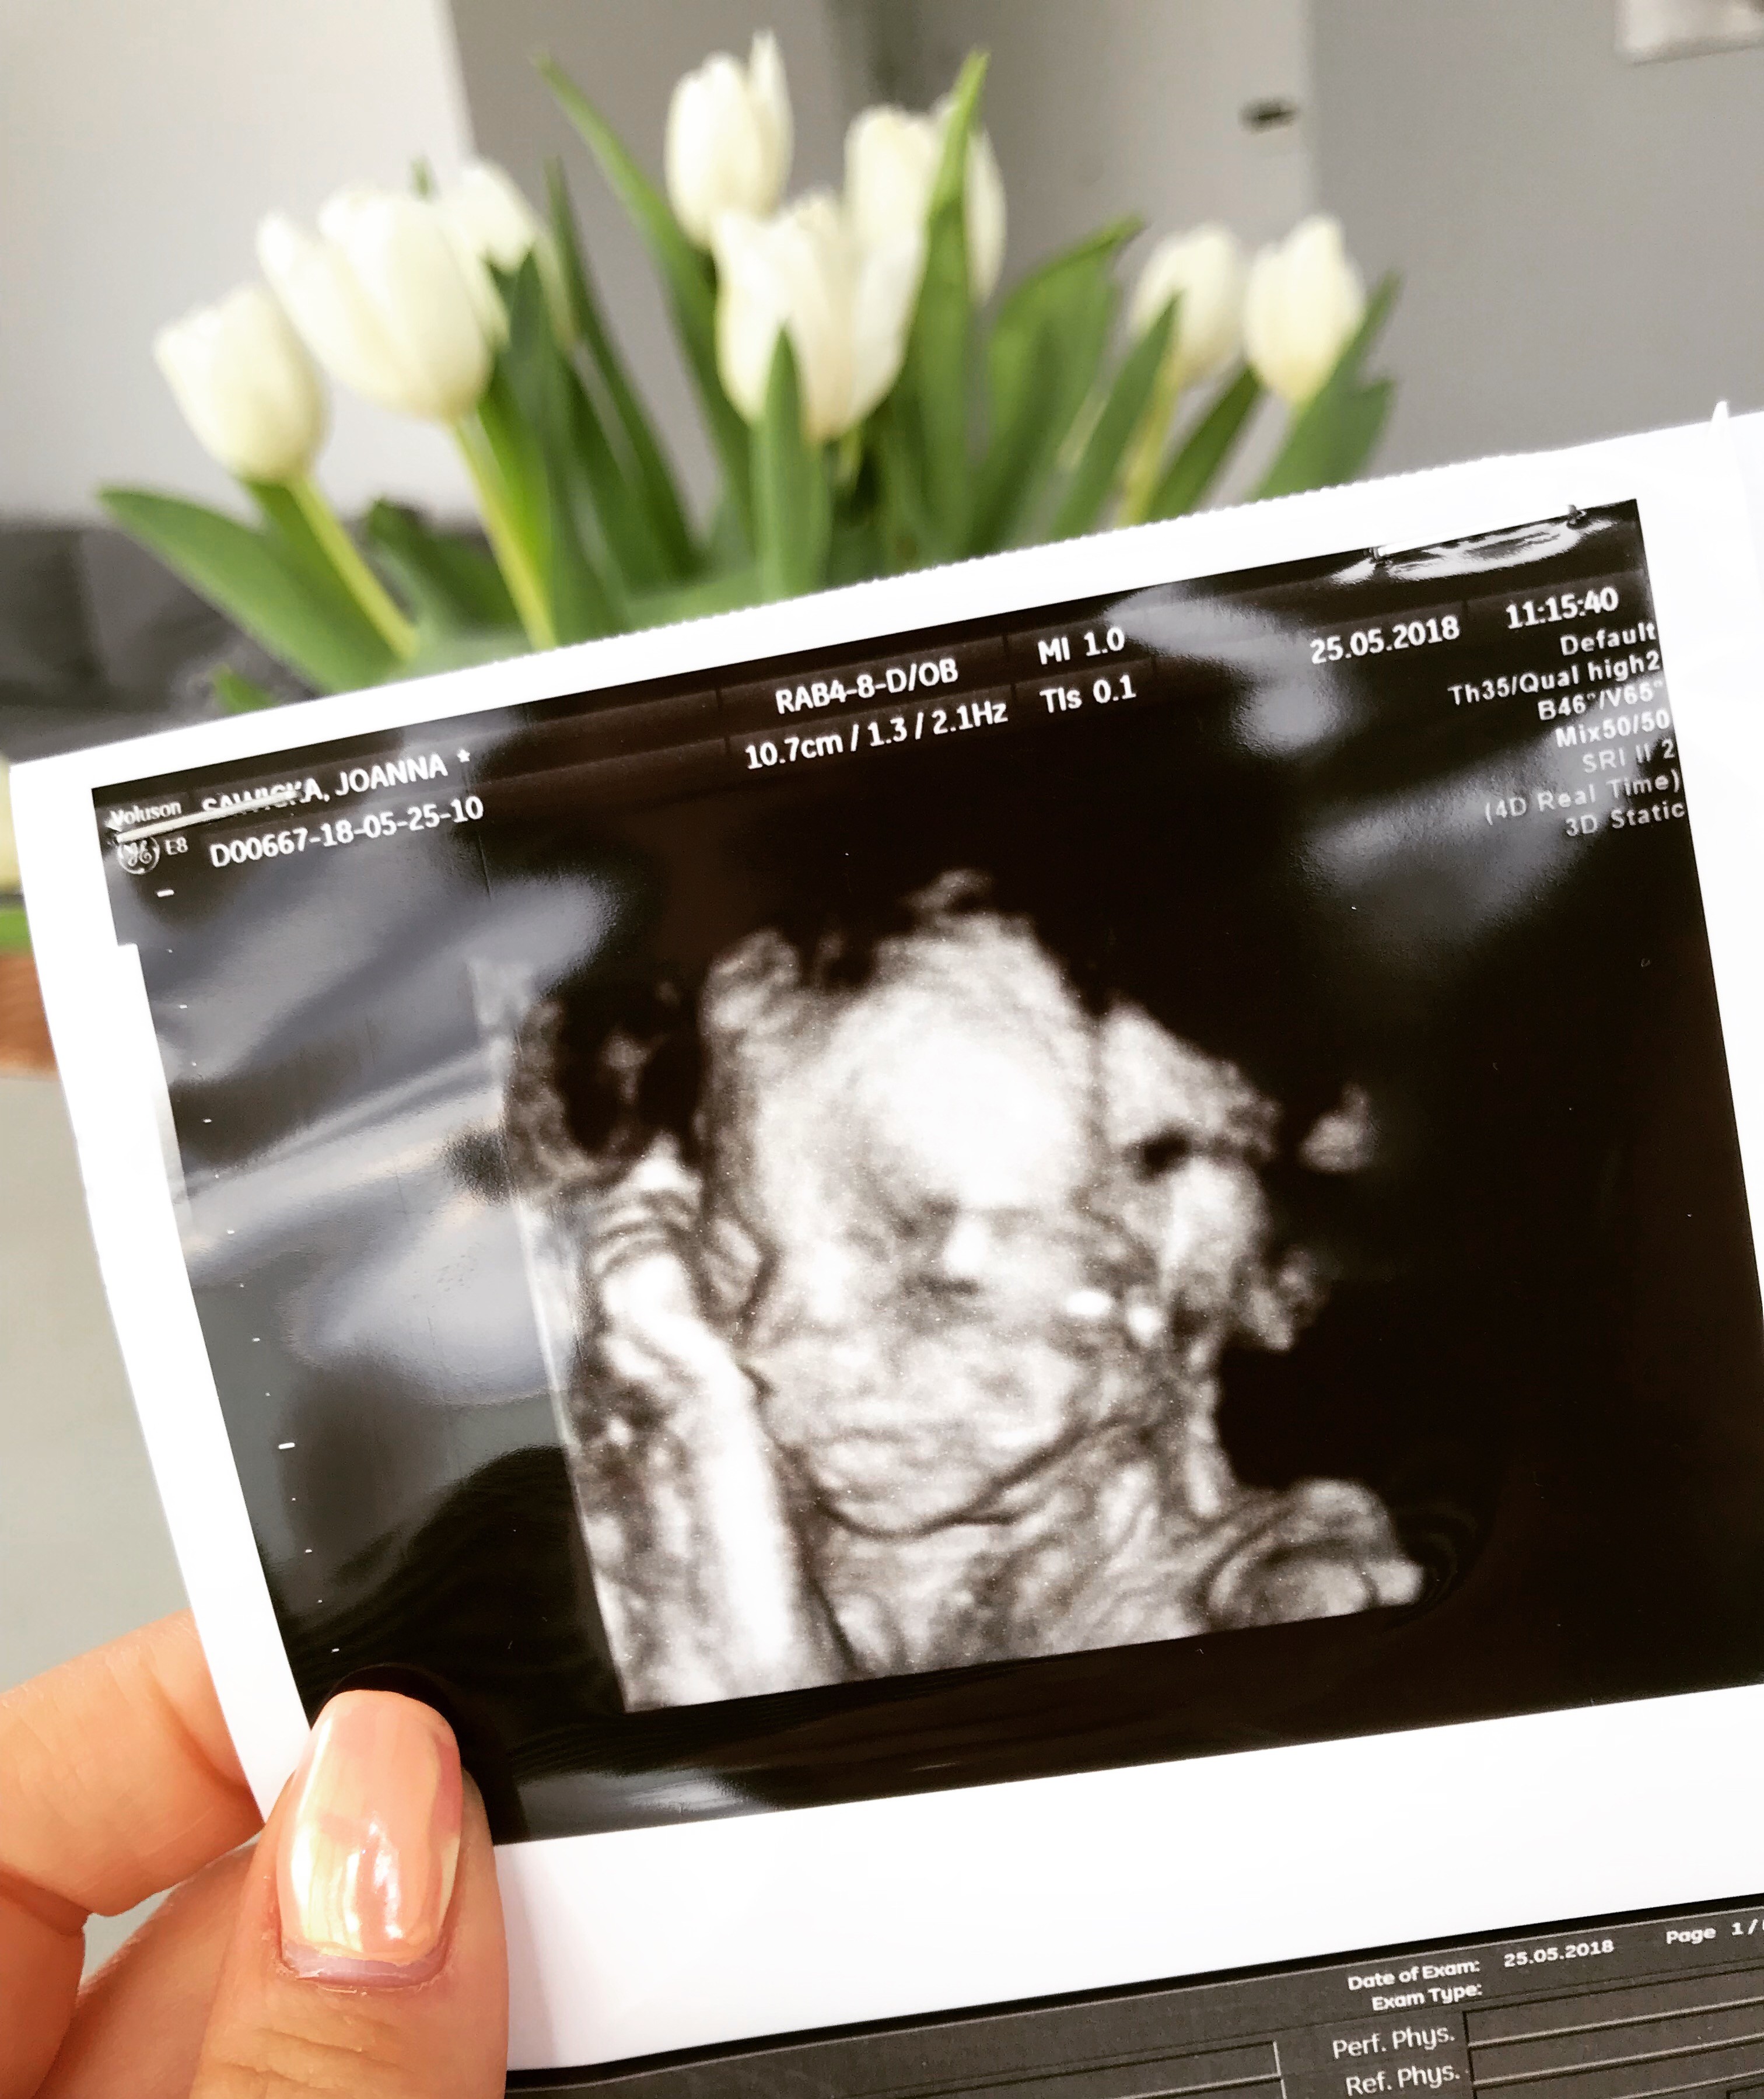

Hej ja po wizycie , dziewczyna 400g , wszystkie parametry w normie , bardzo ruchliwa w trakcie badania :happy:, łożysko z tylu, już się trochę podniosło... badanie wykonane w 20tc i 5 dni

• EC6680E9-67D5-4B85-A807-84D48F3C9285.jpeg

EC6680E9-67D5-4B85-A807-84D48F3C9285.jpeg

1,3 MB · Wyświetleń: 543